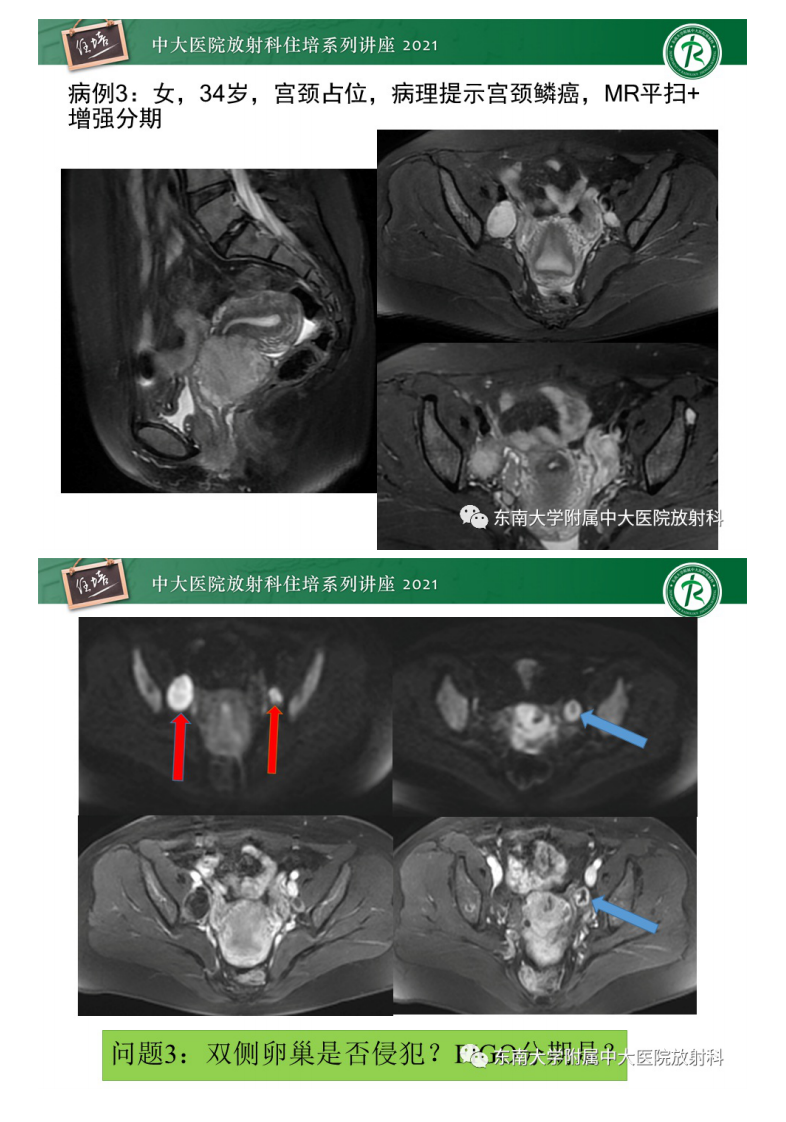

20210627_2【中大放射住培系列讲座】卵巢黄体及相关疾病诊断及鉴别.pdf